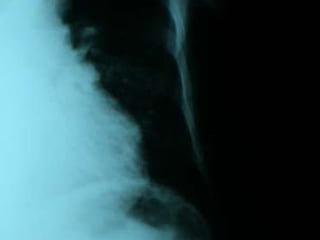

Raio X de Tórax:PA e Perfil Pulmões pouco expandidos,estrias densas no lobo superior do pulmão direito. Infiltrado para-hilar no pulmão esquerdo. Área cardíaca aumentada e seios costofrênicos pérvios.  A partir desse laudo mais o raio x revelando novo infiltrado em lobo superior direito e inferior esquerdo foi constatada Pneumonia Grave Hospitalar provavelmente por Stafilo. Obs : Estava programada alta para o paciente mas o msmo evoluiu com piora do estado geral ,tosse com hemoptóicos. Conduta ; Iniciou Ceftazidime e Ciprofloxacina.

Raio X deTórax:PA e Perfil Pulmões pouco expandidos,estrias densas no lobo superior do pulmão direito. Infiltrado para-hilar no pulmão esquerdo. Área cardíaca aumentada e seios costofrênicos pérvios. A partir desse laudo mais o raio x revelando novo infiltrado em lobo superior direito e inferior esquerdo foi constatada Pneumonia Grave Hospitalar provavelmente por Stafilo. Obs : Estava programada alta para o paciente mas o msmo evoluiu com piora do estado geral ,tosse com hemoptóicos. Conduta ; Iniciou Ceftazidime e Ciprofloxacina.